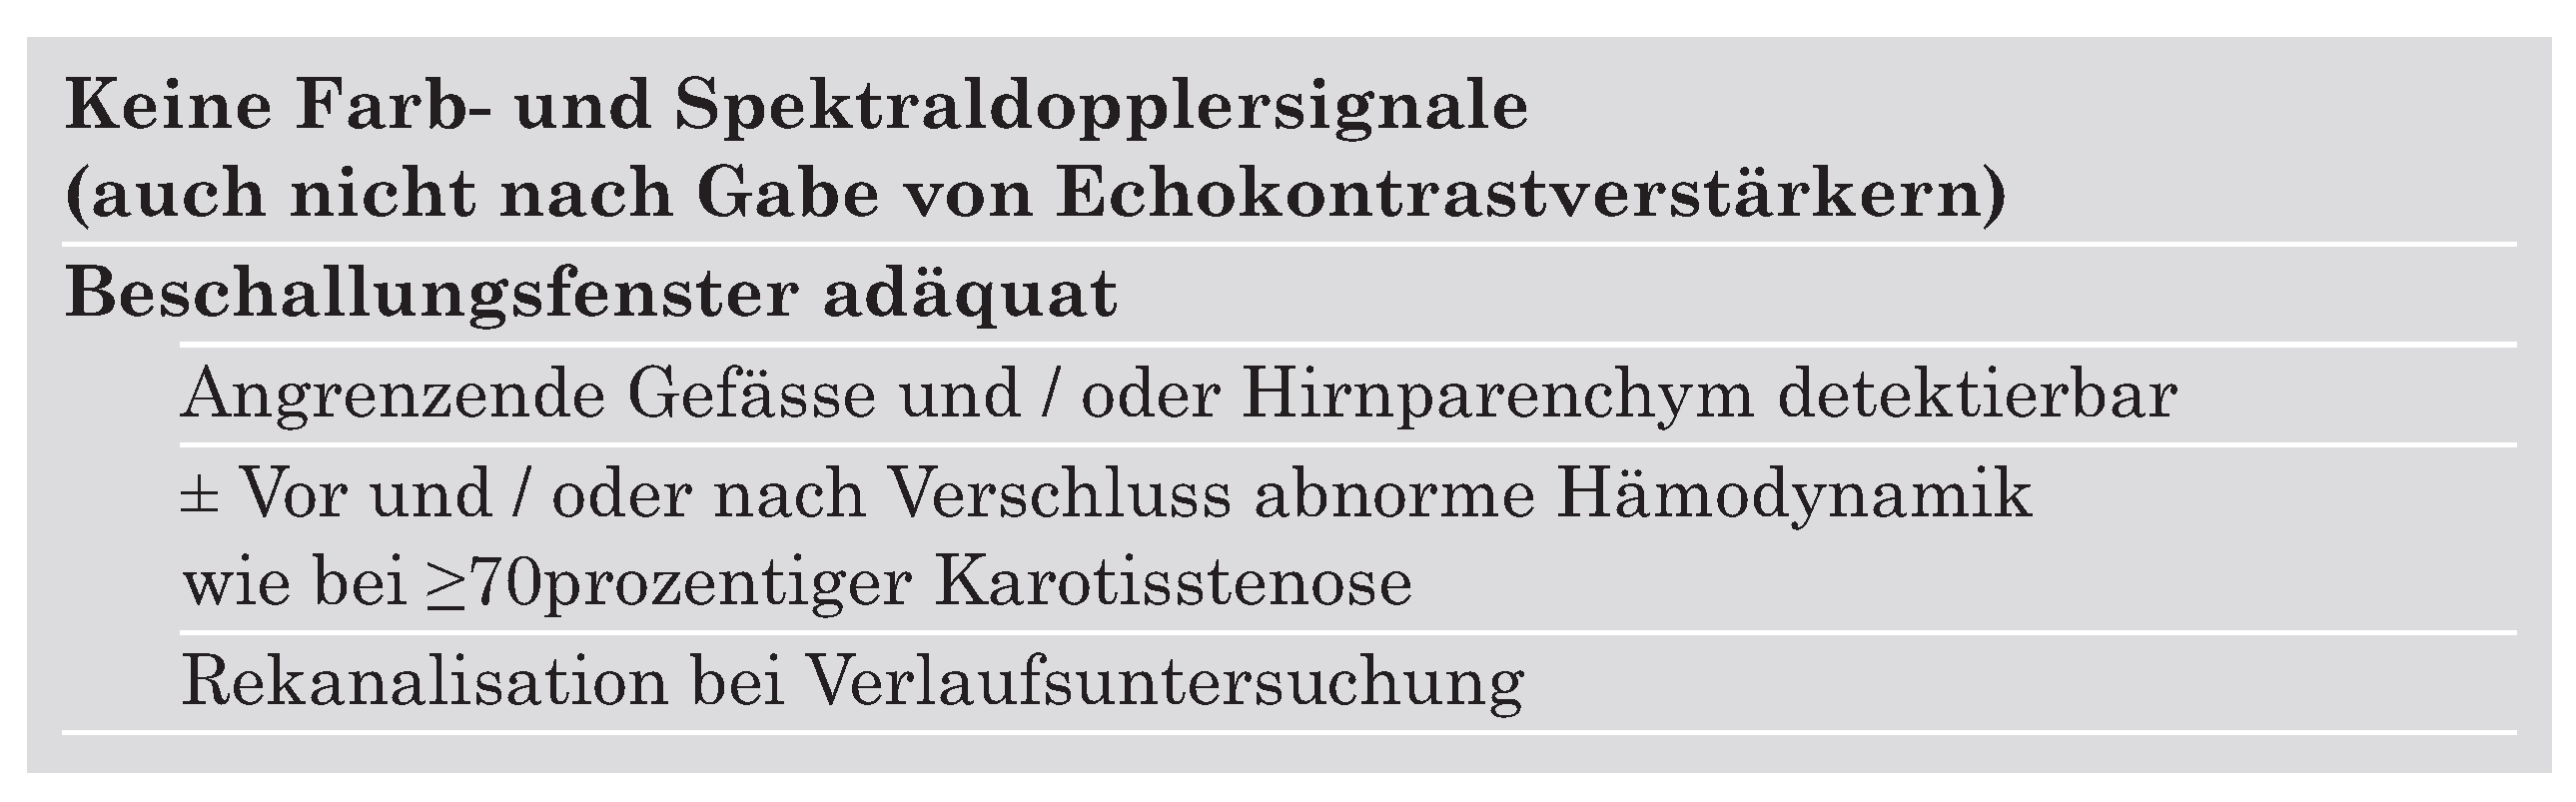

Ultrasonographische Verfahren